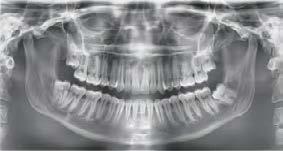

Figura 1. Radiografía panorámica inicial del caso donde observamos el defecto óseo alrededor del ápice de la pieza 11.

El defecto circunferencial recubre todo el ápice y hace que la tabla vestibular se encuentre ausente en prácticamente toda la superficie radicular además de dejar un remanente palatino de menos de 2 mm.

Presentamos el caso de un paciente varón de 47 años, que acude a la consulta dental por presentar dolor, movilidad y fístula en la pieza dental 11. Este caso, fruto de un traumatismo previo, tuvo que ser endodonciado y posteriormente realizada sobre el mismo una apiceptomía, para abordar un quiste apical residual que no terminaba de evolucionar de forma favorable. El trabajado de rehabilitación posterior se llevó a cabo con una reconstrucción con poste y una carilla cerámica. Tras varios años, el diente ha comenzado de nuevo con los síntomas anteriormente descritos por lo que se sospecha la presencia de una fractura radicular. La

radiografía panorámica inicial para el diagnóstico nos aporta una imagen radiolucida entorno al ápice del diente en posición 11 ( Figura 1 ). Para conocer mejor el alcance de la lesión y las opciones terapéuticas de las que disponemos se lleva a cabo un cone-beam en el que se puede objetivar de forma precisa el defecto apical al diente. Este defecto es circunferencial y está dejando una reabsorción casi completa de la tabla ósea vestibular y parcial de la palatina, con un grosor de 1.9 mm, como vemos en el corte seccional (Figura 2). Si observamos la medida total en la zona media del incisivo dentral, necesitamos cubrir una anchura aproximada de 8 mm por lo que el implante que coloquemos irremediablemente dejará un gap, que según los protocolos quedará en vestibular. Utilizando una plataforma estándar de 4.1 mm el gap a rellenar será prácticamente de 4 mm según las medidas que nos